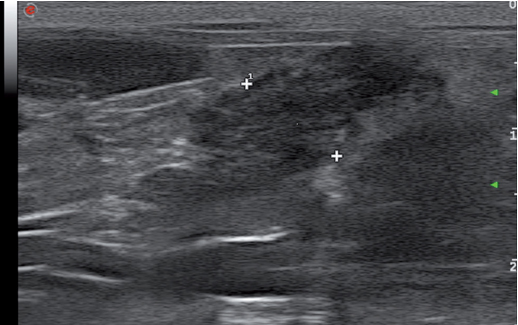

急性胰腺炎,慢性胰腺炎及无任何胰腺炎症状的老年猫都可见胰管扩张,所以超声影像发现胰管扩张不能作为诊断胰腺炎的指征(图14)。胰管扩张也可见于结石性疾病。此外,胰腺炎造成的总胆管扩张,最后可能会导致胆囊扩张。